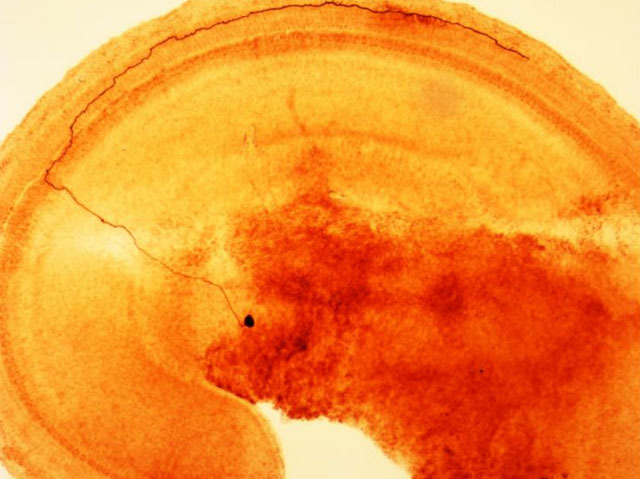

The inner ear is a delicate structure, generating the sensation of sound thanks to fragile hair cells, detecting the pressure of sound waves. Sensory neurons, known as type I afferents, then transmit the signals from the hair cells to the brain. However, very loud noises can destroy hair cells, permanently degrading our sense of hearing. Type II afferent neurons are relatively insensitive to sound, but respond when outer hair cells, those closest to danger, are damaged; like pain receptors in the skin, their role is to warn the brain, so that we can protect ourselves before more cells are lost. In the rat’s inner ear shown, a type II afferent stretches from the outer hair cells to the brain, where its cell body forms a dark spot near the centre of the picture. Studying how these neurons operate could provide new insights into hyperacusis, a painful hyper-sensitivity to noise.